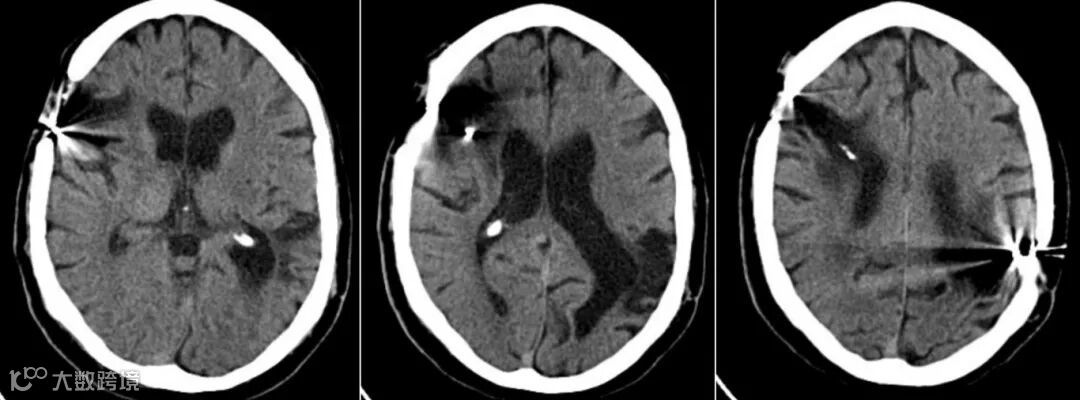

男,30岁,子弹从右向左移动,伴有颅骨骨折、脑挫、裂伤,脑内气肿、脑室积血、弥漫性脑水肿及多发弹片残留。

脑室受压、中线移位提示颅内压升高;

蛛网膜下腔出血表现为脑沟、脑池内高密度影。